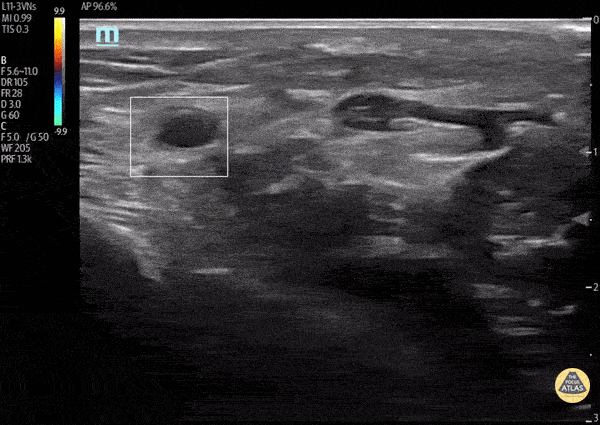

A middle aged male with history of hypercoagulability and recent cardiac catheterization utilizing radial artery access, presented with right arm pain, numbness and tingling. POCUS revealed a complete occlusion of the distal right radial artery. The patient was started on anticoagulation therapy initially, with plan for potential thrombectomy with interventional radiology Kathrin Parisi, MS-IV; Courtney Hollingsworth, MD; Therese Mead, DO, RDMS, FACEP; Matt French, DO - Central Michigan University